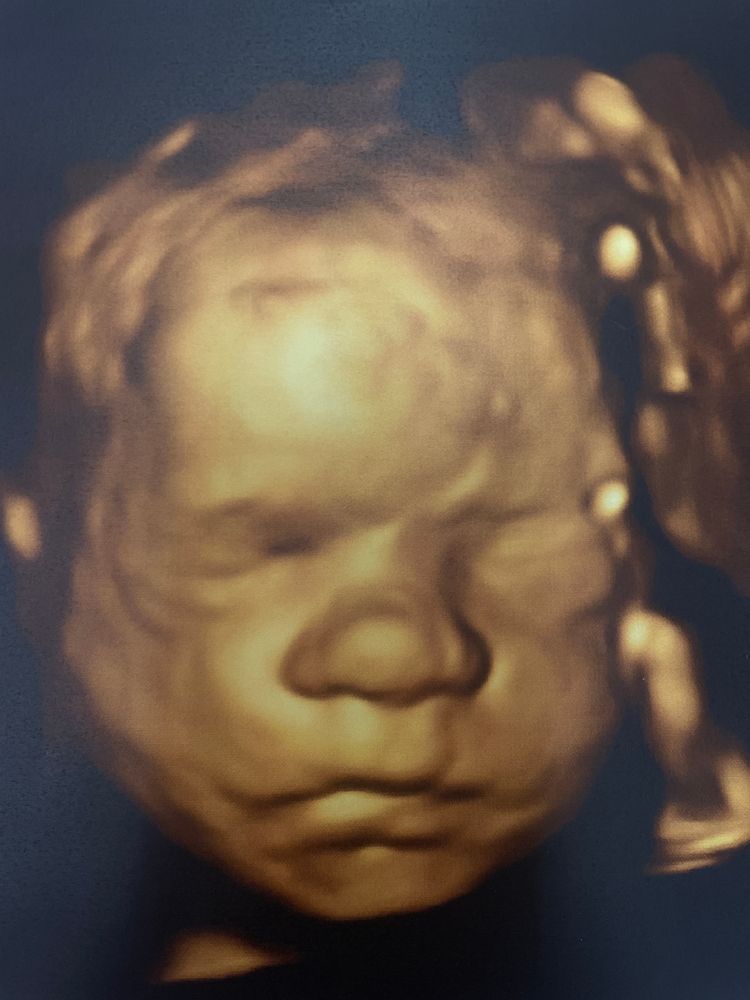

4Д УЗИ 🙏🏻

На 3-х предыдущих УЗИ дочь всегда лежала или затылком к датчику, или лбом в живот 😄 Поэтому я переживала, что 4Д снимки не получатся)) Ну, в начале так оно и было)) Ноги лежали на голове и закрывали лицо😄 Но позже мадам соизволила показаться ❤️

Собственно, нос, губы и вечно хмурые брови у нас в отца😄 Еще и в его день рождения намеревается родиться, по всей видимости)) срок по УЗИ, как всегда, на неделю больше. И если считать по нему (27нед 4 дня), то ПДР выпадает точно в день рождения мужа - 17.10👌🏻 Он, конечно, очень хочет поделиться с ней своим днем. Странный 😁

Сказали, что будет высокая девчонка. Ноги аж на 28.6🙈 Вес 1140гр.